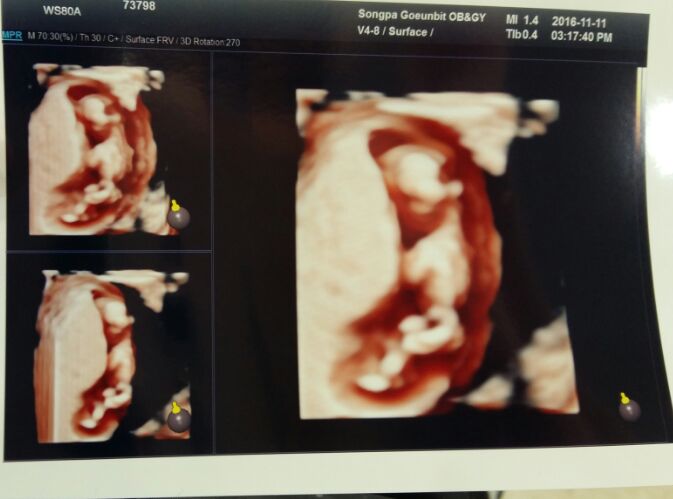

보름이의 육아일기♡ - 12주 초음파

2016.11.12 보름이가 벌써 12주차가 되었다..ㅎ 시간 참 빠르네잉아들일까 딸일까 폭풍검색 ㄱㄱ 12...